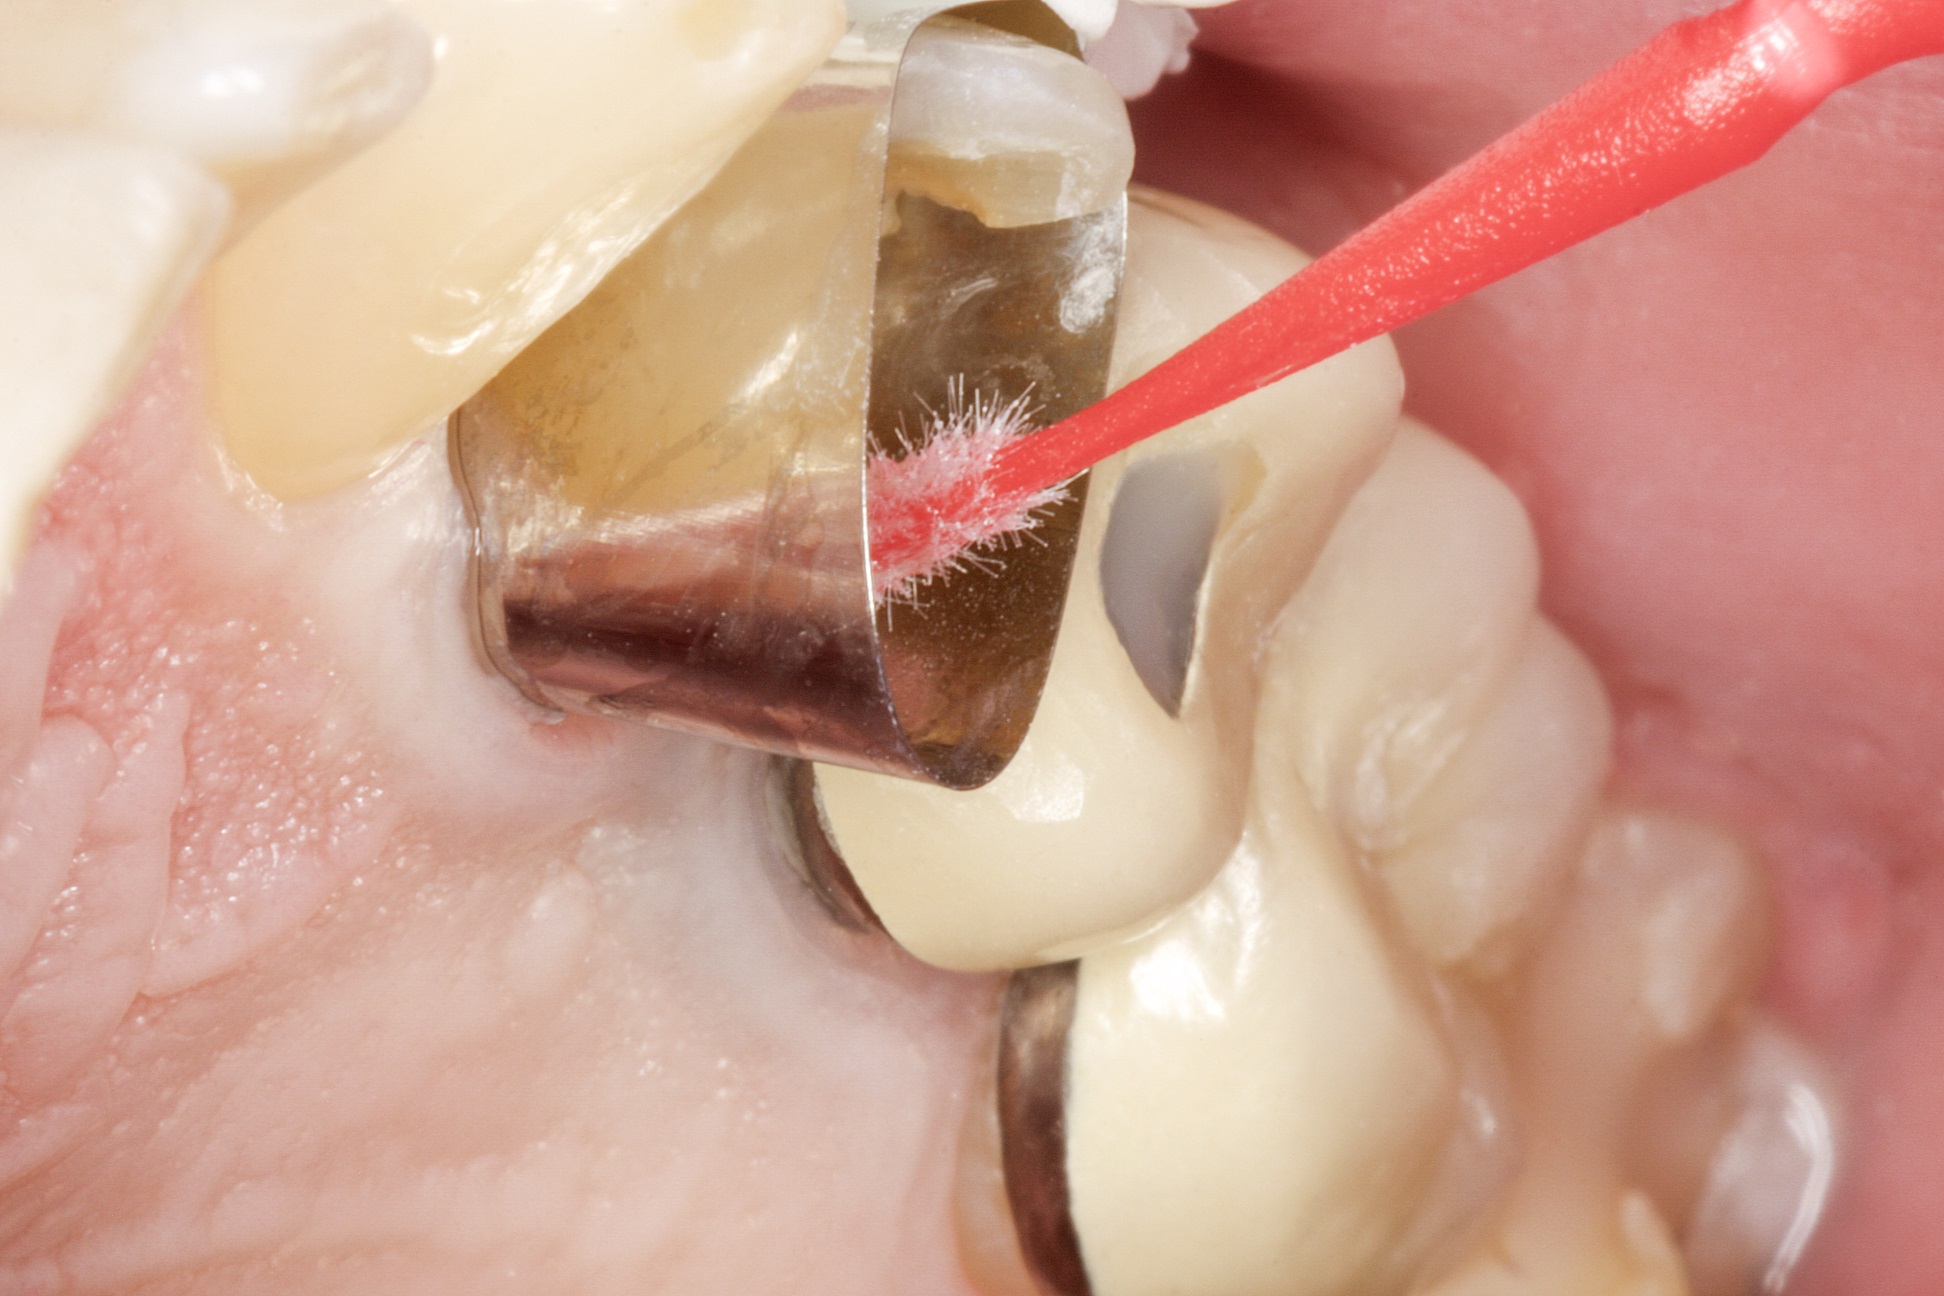

На зуб встановлюється одноразова матриця типу

Tofflemire (OmniMatrix, Ultradent). Весь підготовлений зуб протруюють

ортофосфорною кислотою протягом 20 секунд (рис. 4), а потім ретельно промивають

водно-повітряним спреєм. Після цього канали просушують паперовими штифтами.

Фото 4. Протруювання

зуба ортофосфорною кислотою.

Відпрепарована зона повністю обробляється адгезивною

системою LuxaBond відповідно до інструкції виробника (рис. 5).

Фото 5. Використання

адгезивної системи LuxaBond.